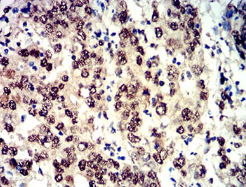

Phospho-4E-BP1 (Ser65)单克隆抗体[2D1G1]

Phospho-4E-BP1 (Ser65) Mouse Monoclonal antibody[2D1G1]

FCM    1/200 - 1/400